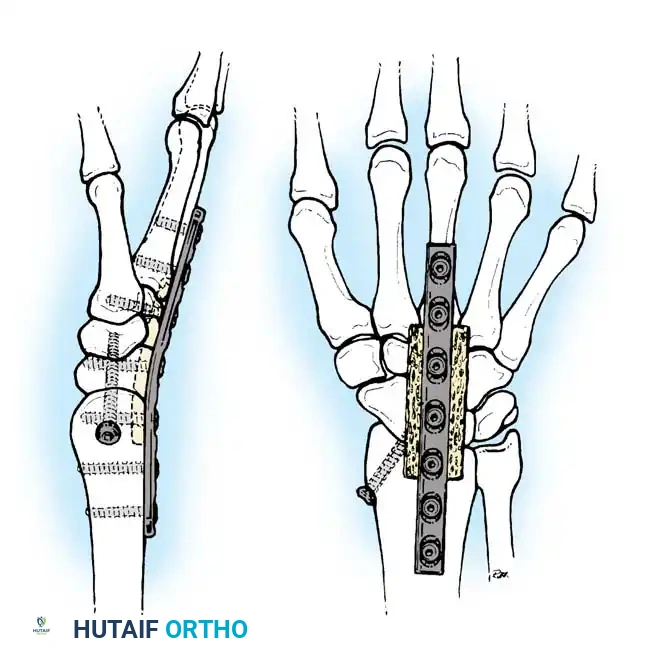

Tendon graft routing through osseous tunnels in the radius and ulna for anatomic reconstruction of the DRUJ ligaments.

In chronic settings where the TFCC is irreparable, anatomic ligament reconstruction using a tendon autograft (e.g., palmaris longus) is indicated. The graft is routed through the distal radius and ulnar fovea to recreate the dorsal and volar radioulnar ligaments.